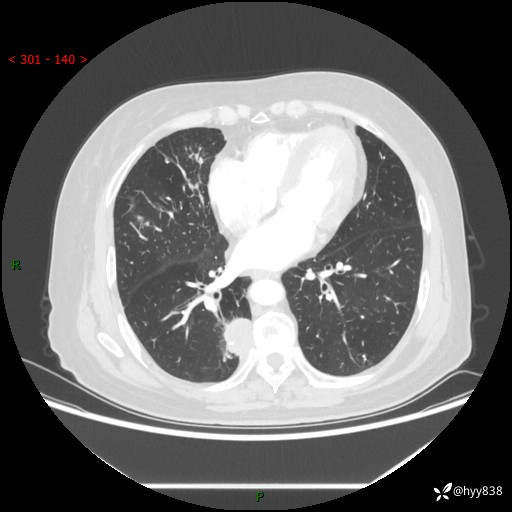

胸部CT肺窗(平扫外院)

增强动脉期+静脉期

两期CT值:55Hu 53hu